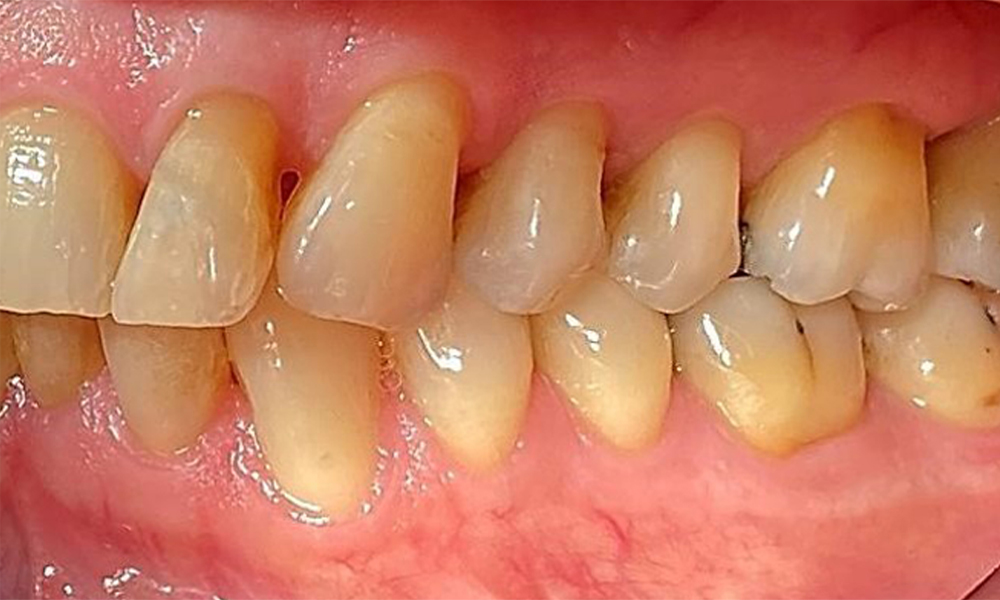

Left lateral view including the recessions.

Fig. 4 Left lateral view including the recessions. © Dr R. Krapf

The patient has a full dentition with 28 teeth, which includes amalgam and composite fillings in the molar and premolar regions. There is a visible clinical marginal gap present on tooth 14. Tooth 27 has an adequate gold inlay. There are also generalized attritions and abrasions. (Fig. 2, Fig. 3, Fig. 4, Fig. 5, Fig. 6)

The patient has stage II, grade B periodontitis (5). At 1 to 3 mm, the clinical probing depths were within the physiological range. Localized probing depths of 5 mm were observed on the mesiopalatal aspects on both 17 and 27. There are generalized recessions of 1–3 mm with partial loss of the interdental papillae (Fig. 2, Fig. 3, Fig. 4)